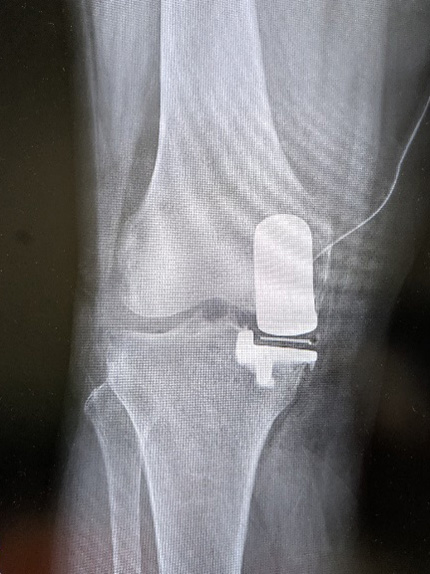

単顆部膝関節置換術 (UKA)

• 単顆部膝関節置換術 (UKA)

痛みが膝の内側か外側かに現局している場合にはUKA行います。

骨の変形が軽度で、膝関節の可動域がよく、靭帯が傷ついていない場合が適応になります。

人工関節全置換術(TKA)に比べて、皮膚の切開が小さく、骨の切除量が少なくなります。